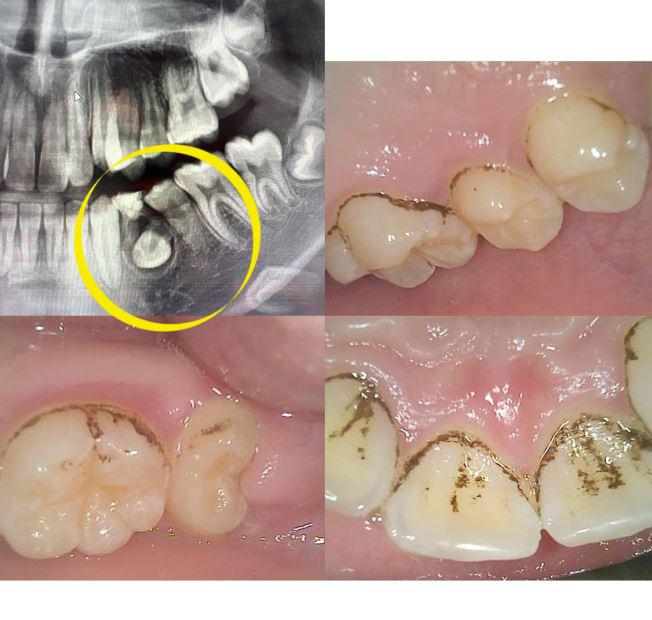

초등6학년 이빨ct촬영사진입니다.

이빨 노란색 표시된부분 흔들리지는 않는데 , 어떻게 치료해야하나요?

고견을 구합니다.